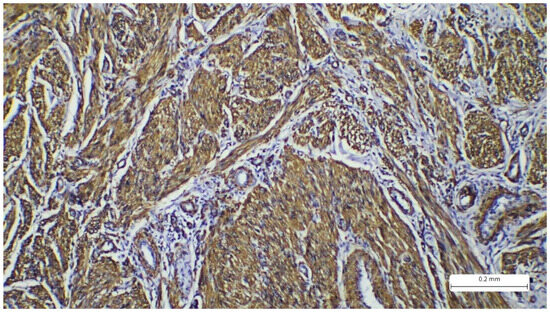

2. Case Report